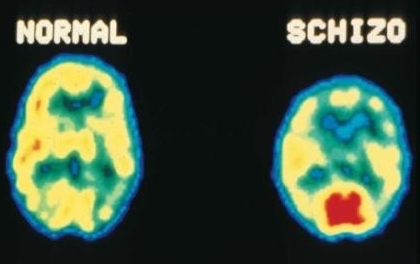

A esquizofrenia é um transtorno mental crônica na qual realidade e imaginação se confundem. A pessoa com esquizofrenia tem a sensação de estar sendo perseguido e/ou vigiado, além de ouvir vozes que o atormentam. Mas podem ter outras alucinações, como: visuais, táteis, olfativas, gustativas e até todas juntas. As pessoas próximas começam a perceber que o transtorno também altera o lado afetivo e mental do doente, ou seja, não expressa nenhum tipo de emoção e apresenta desorganização psíquica, dificuldade de se concentrar e há uma queda considerável na motivação.

As causas dessa doença são de origem genética, fatores ambientais, alterações no cérebro e no processo bioquímico dos neurotransmissor dopamina.